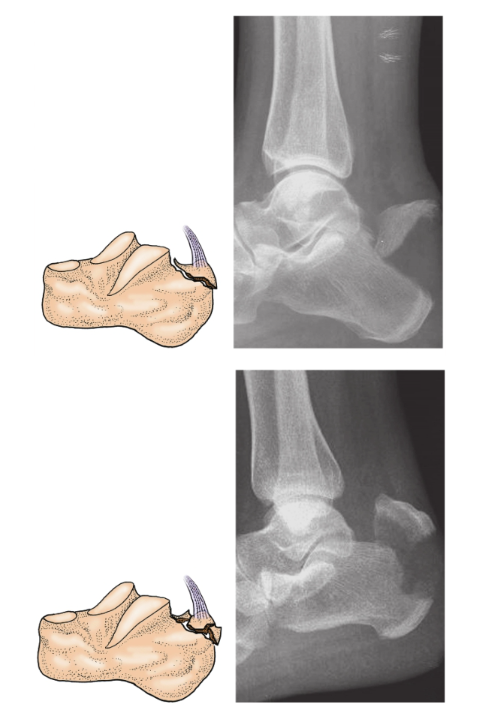

2、跟骨结节骨折:

跟骨结节骨折既可以是跟骨结节后部撕脱骨折也可以是跟骨后上部鸟嘴样骨折,其损伤机制主要是由于小腿三头肌突然猛烈收缩牵拉跟腱附着部所致,少数是由直接暴力引起。跟骨结节骨折临床表现为足后跟部疼痛和肿胀。跟骨结节上方只有少量的软组织覆盖,被撕脱的骨块移位可能会危及周围的皮肤(图7)。

图7 跟骨结节骨折